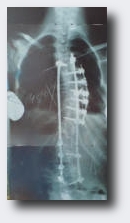

Treatment Brace Surgery

If the named conservative therapy methods don't bring an sufficient success and the progression can't be stopped or exceeds a certain degree than it is time to think about a spine stifling operation. During the operation a pole which is fixed at the spine with some screws will be brought in your body. This very comlicate operation should only be made in hospitals which are specialised on it.